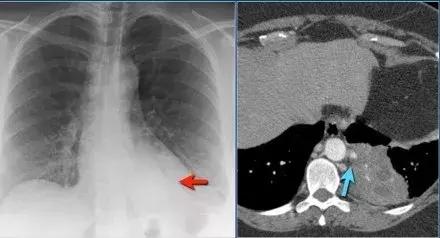

肺栓塞

➢ 急性非动脉血栓栓塞的影像图常变化不显著,而且非特异性。

➢ 对肺动脉血栓(PIOPED)的前瞻性研究发现最常见的影像学特征是肺不张和肺斑片状阴影。

➢ 大多数肺动脉栓塞可有正常的胸部X线

➢ 观察CECT,此患者患有肺栓塞

➢ 在栓塞区域发生外周实变,为栓塞区出血引起

图7 肺栓塞性实变